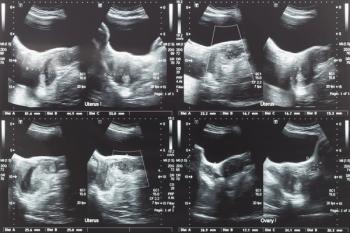

Mauricio Abrão, MD, and Jessica A. Shepherd, MD, MBA, FACOG, comment on the use of diagnostic tools and the importance of imaging in approaching the treatment of uterine fibroids.